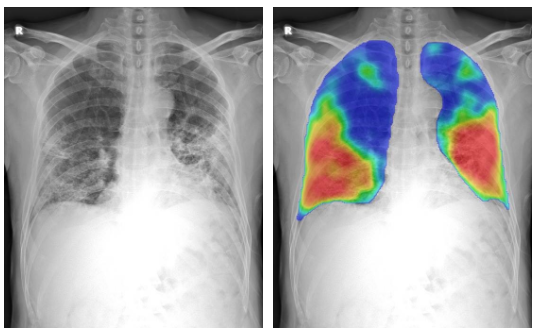

Free AI-software for Covid-19 triage on chest x-rays